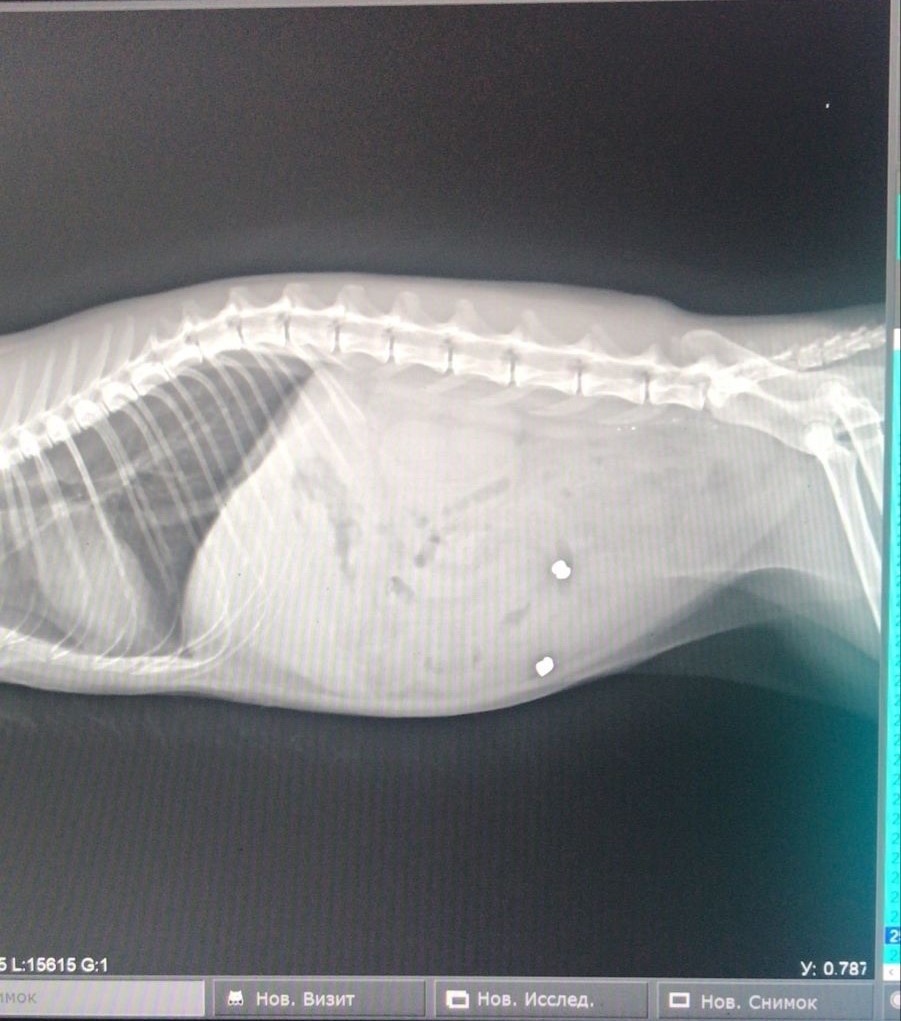

На фото вы видите рентгеновский снимок кота, в которого стреляли.

Пули были выпушены в область задних конечностей, а затем попали в брюшную область.

Любимец провел в таком состоянии неделю, а затем попал к нам на прием.

На фоне длительного нахождения пуль в организме кота и присоединения вторичной патогенной микрофлоры развился перитонит.

Перитонит – это воспаление листков брюшины.

Листки брюшины представляют собой ткани, которые выстилают внутреннюю поверхность живота (париетальный листок брюшины) и покрывают большую часть органов брюшной полости (висцеральный листок брюшины).

В следствии этого, животное пришлось "усыпить", так как шансов на излечение уже не было.